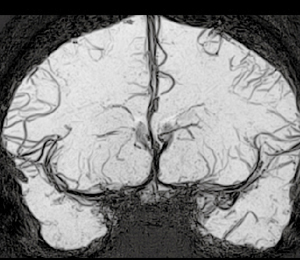

◆FSBBから進化したHOP-MRA

FSBB(Flow-Sensitive Black Blood)法は,血液を低信号化する目的で弱いMPGパルスを与えたグラディエントエコーシーケンスでT2強調の特性も併せ持ち,磁化率のみならずフローにより血管-背景コントラストをつけることが可能な方法である。FSBBは,特に低速の“flow”を高感度に描出する特長があり,臨床的には腫瘍性病変や血管性病変に使われている(図1,2)。さらに,断面に依存せずflow情報を取得できるため,従来法では描出が難しいとされてきた大脳基底核穿通枝動脈の描出も可能である(図3)。FSBBは,空間分解能も従来のTOF法の3D-MRAと同等以上を実現することが可能で,最小値投影(mIP)処理することでより高精度な観察が容易になる。

図3 健常人における1.5T大脳基底核穿通枝動脈の描出

(画像ご提供:京都大学医学部附属病院放射線診断科・岡田知久先生)